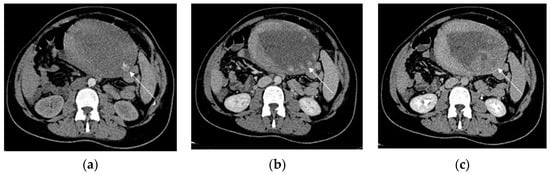

Contrast-enhanced CT should be performed to detect and localize active bleeding that appears as extravasation of the contrast agent. Significant arterial bleeding can be identified on the arterial phase, while small arterial or venous oozing can be detected during the delayed phase (Figure 8) [97].